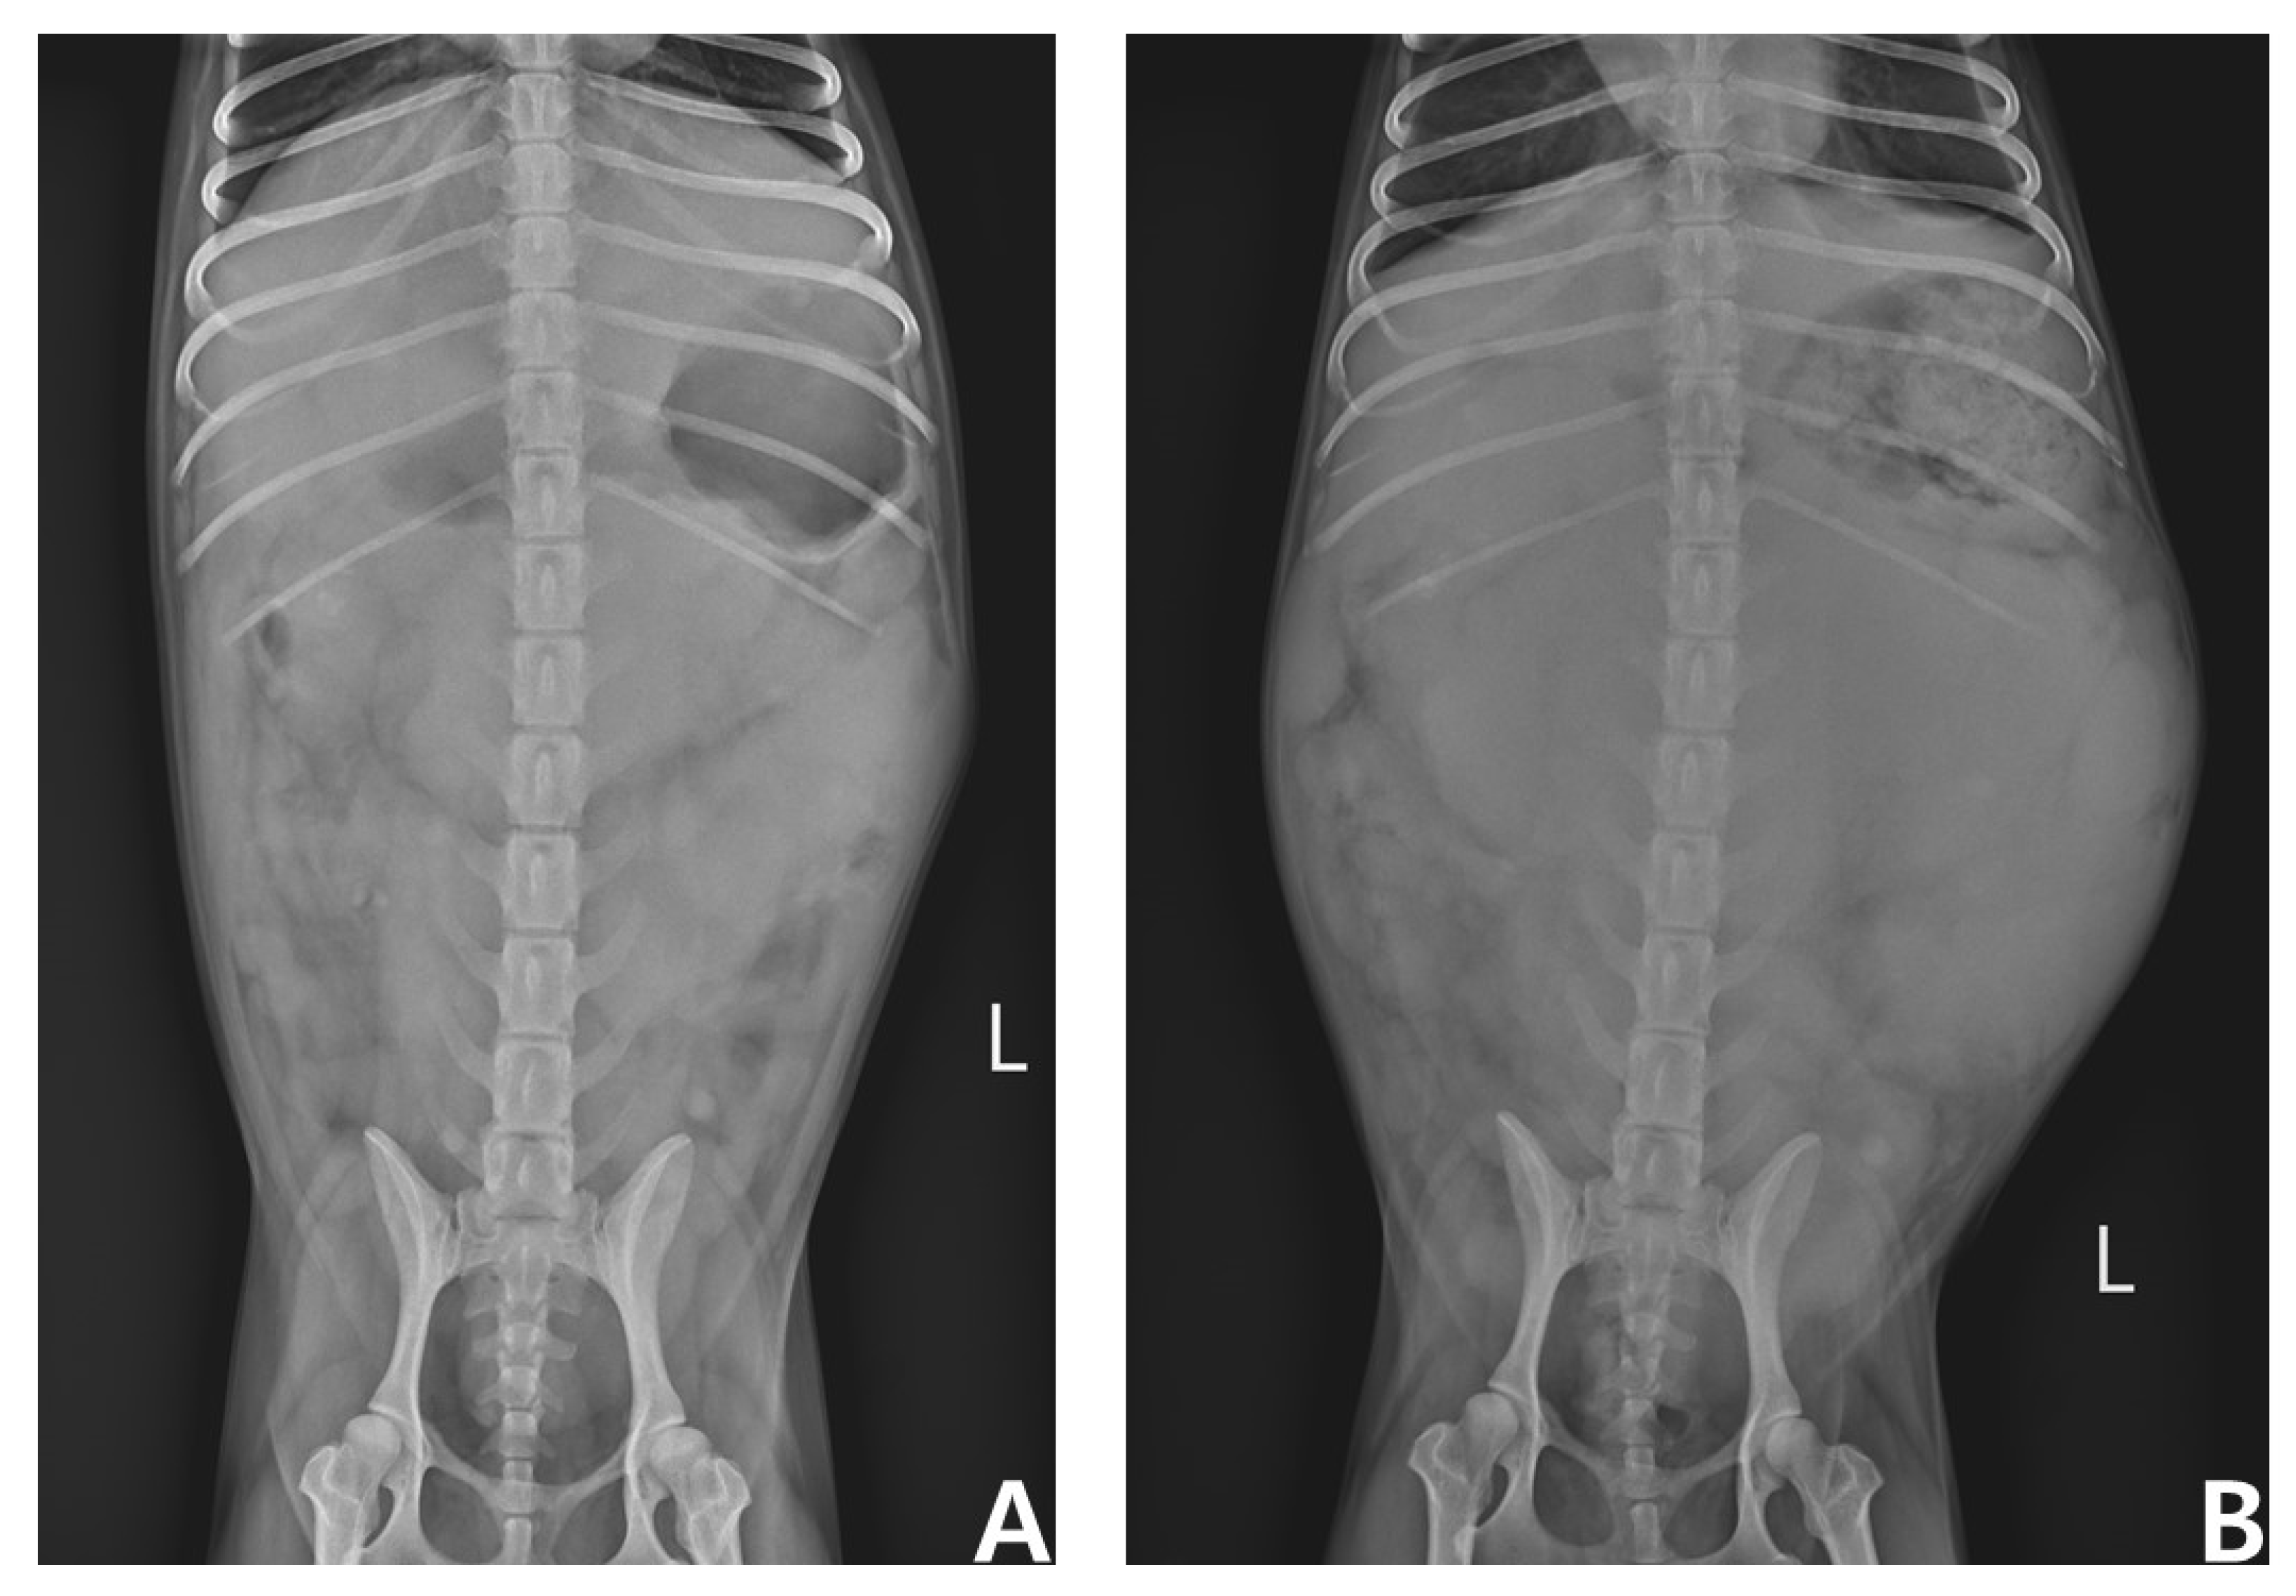

2. Case Presentation